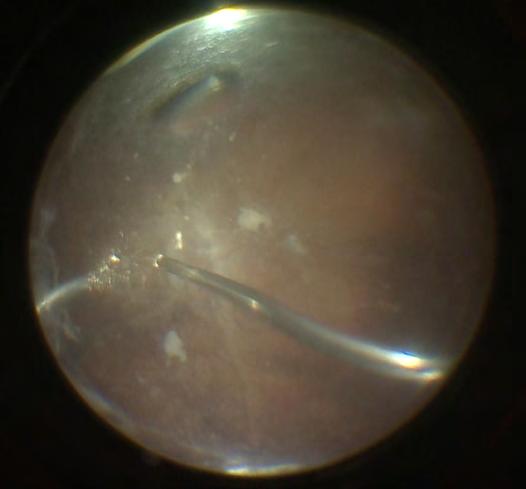

Quando la sola luce pulsata non é sufficiente si puó associare la Tecnica di Maskin, il Probing 1 delle Ghiandole del Meibomio, per ripulirle dai sedimenti che possono averle occluse oppure il Probing 2 dove, oltre ad aprire le ghiandole viene iniettato in ognuna

di esse un collirio antibiotico cortisonico o PRP. L’ultima novità tecnologica disponibile dal 2023 in Italia si chiama JETT-PLASMA.

Probing

Questa tripla azione è molto utile per il trattamento della MGD perché svuota le ghiandole dal Meibum denso e le ringiovanisce in modo che possano produrre un Meibum chiaro e oleoso.